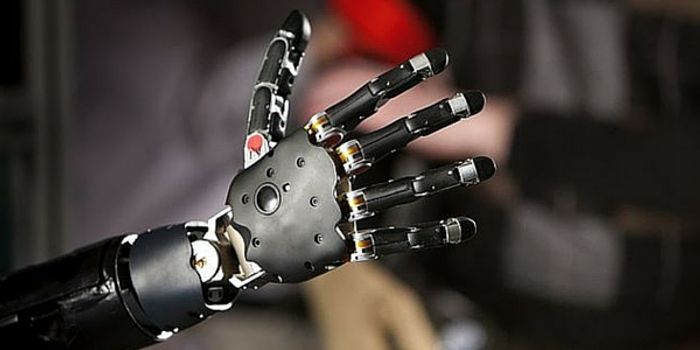

MAR 03, 2016NeuroscienceAs a result of the war in the Middle East, there are 1,558 American soldiers who have suffered the loss of a limb. Add t ...

MAY 21, 2015NeuroscienceRobotic prosthetic arms are gaining a lot of recent interest after neuroscientists at the California Institute of Techno ...